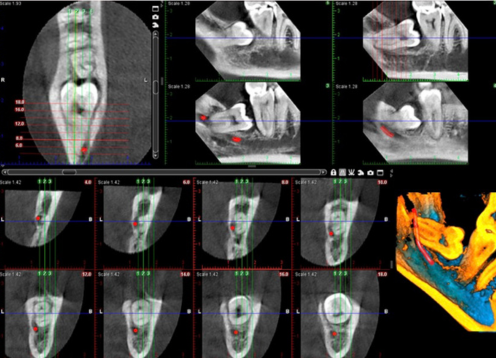

Dental imaging is often used for diagnosis and treatment planning. They provide dentists with highly detailed images of teeth, jaw bones, airways, nerves, blood vessels, and soft tissues.

With our tool, the Planmeca ProMax® 3D Classic, a clear view of the mandible and maxilla is captured making it an excellent option for full arch dental 3D imaging needs.

3D dental scans can help dentists diagnose and plan treatment for oral health concerns. 3D images are more detailed and can show the complex anatomy of a root canal system. They can also help dentists identify teeth that need to be shifted for proper alignment. Other key benefits include :